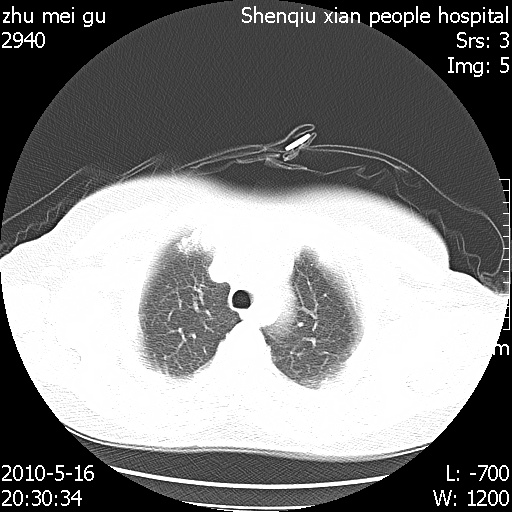

标题: CT26733:能否诊断支扩?

患者,女,62岁,有反复咯血史10年,近三年来大咯血数次,每次量在500-1000ml

图像不全。右中叶内侧段纤维、钙化灶。

没看到支气管扩张的证据

you右肺中叶有点支扩 但不至于咳那么多血啊

图像不全,不像支扩。

不能诊断支气管扩张!

右中叶内侧段慢性感染性病变,不排除合并支气管扩张可能。